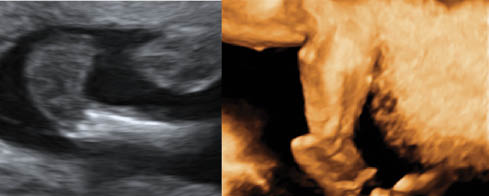

careful examination of the hands and feet are very helpful as most of the cases with trisomy 18 are associated with limb posture abnormalities